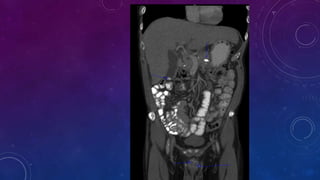

• Other than granuloma think of other causes for

liver and spleen calcifications.

• Evaluate chart for any treated lymphoma as in this

case here.

• Multiple pelvic phleboliths.

• Small well-defined round osseous lesions in the left

side of the abdomen, adjacent to midline represent

calcified lymph node in the para-aortic and left

common iliac groups, also visualized on the

corresponding CT.